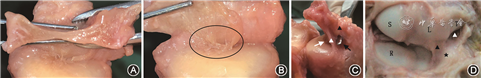

1.TFCC解剖:自腕关节尺背侧切开,切断并牵开伸肌腱,掀起背侧关节囊后,观察TFC桡侧附着部的完整性并沿桡骨远端乙状切迹切断。使腕关节屈曲,显露并观察尺月韧带、尺三角韧带的连续性,后自二者与TFC移行部锐性切断。此时可将尺腕关节脱位,将TFC自桡侧掀起,观察有无中心型穿孔及掌背侧浅层裂伤;若无穿孔,测量TFC中央部最纤薄部位的厚度,测量3次并取均值(图1A);存在穿孔时,TFC厚度记为0 mm。观察DRUL浅层纤维于尺骨茎突尖部的止点是否连续;向尺侧掀起TFC,观察掌背侧DRUL深层纤维于尺骨茎突凹处的止点是否连续,并用探针探查浅、深层止点间是否存在血管化纤维组织(图1B)。

1.TFC:TFC的解剖形态为一双凹面三角形,中间薄边缘厚,横断面呈哑铃型(图3A)。该形态特点是在TFC所受应力作用下形成的。由于TFC最重要的功能为缓冲尺月间的应力传导,其中心区域承受应力最大,故常厚度最小或出现穿孔。在MRI冠状位或矢状位的图像中,TFC均呈现为双凹面低信号结构。当出现穿孔时,低信号中断,穿孔区域出现高亮信号,或由于穿孔周围纤薄,图像中可见尺骨及月骨的软骨面直接接触。

2.DRUL:DRUL起自桡骨乙状切迹,分为掌侧和背侧韧带,走行于TFC的掌背侧边缘。大体解剖中,难以将韧带自软骨盘剥离,其形态为软骨盘掌背侧边缘的增厚部分。DRUL分为浅层纤维(d-c)和深层纤维(p-c)。掌背侧浅层纤维走行至TFC尺侧后汇合,止于尺骨茎突尖部。而深层纤维行至尺侧后转向近端,止于尺骨茎突凹。其作用是对TFC起锚定作用,从而维持TFC的张力并为远尺桡关节提供稳定性。自止点切断深层纤维,可见其止点为环绕尺骨茎突凹的一弧形区域,而并非局限于小凹内部(图3B)。在浅层和深层纤维之间,可见疏松的纤维结缔组织,探针可从间隙内穿过(图3C)。MRI图像中,在冠状位TFC的掌背侧边缘可见同为低信号的韧带结构,其与TFC的区别在于:二者的桡侧起点均为桡骨乙状切迹,TFC为纤维软骨结构,其起点处可见乙状切迹的软骨信号;而DRUL的起点为长入骨内的纤维(Sharpey′s fiber),此处软骨信号消失。DRUL的尺侧止点为低信号纤维结构,理想情况下浅层和深层纤维被中高信号的血管化纤维组织所分隔,但由于尺侧纤维结构细小,且混杂信号多变,现实中往往难以清晰识别。

3.UCL:UCL包括尺月韧带和尺三角韧带。二者起自TFC掌侧边缘增厚处,分别止于月骨和三角骨(图3D)。在冠状位MRI中,可于TFC掌侧层面观察到尺腕韧带;或者在矢状位上,可见自TFC掌侧边缘至月骨和三角骨的低信号韧带结构。